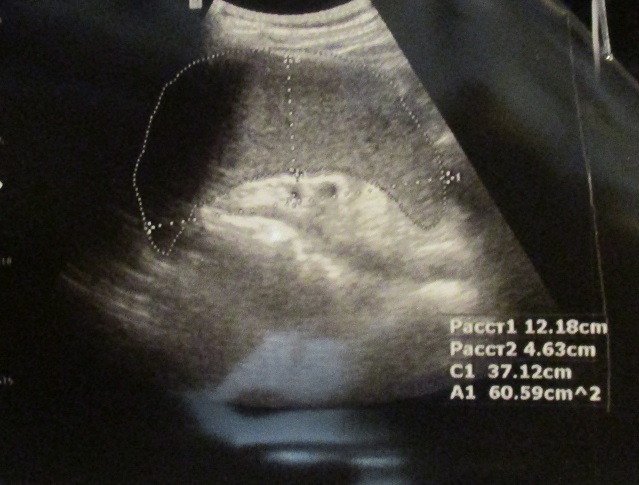

УЗИ брюшной полости.

Вложения

IMG_0584.JPG

IMG_0585.JPG